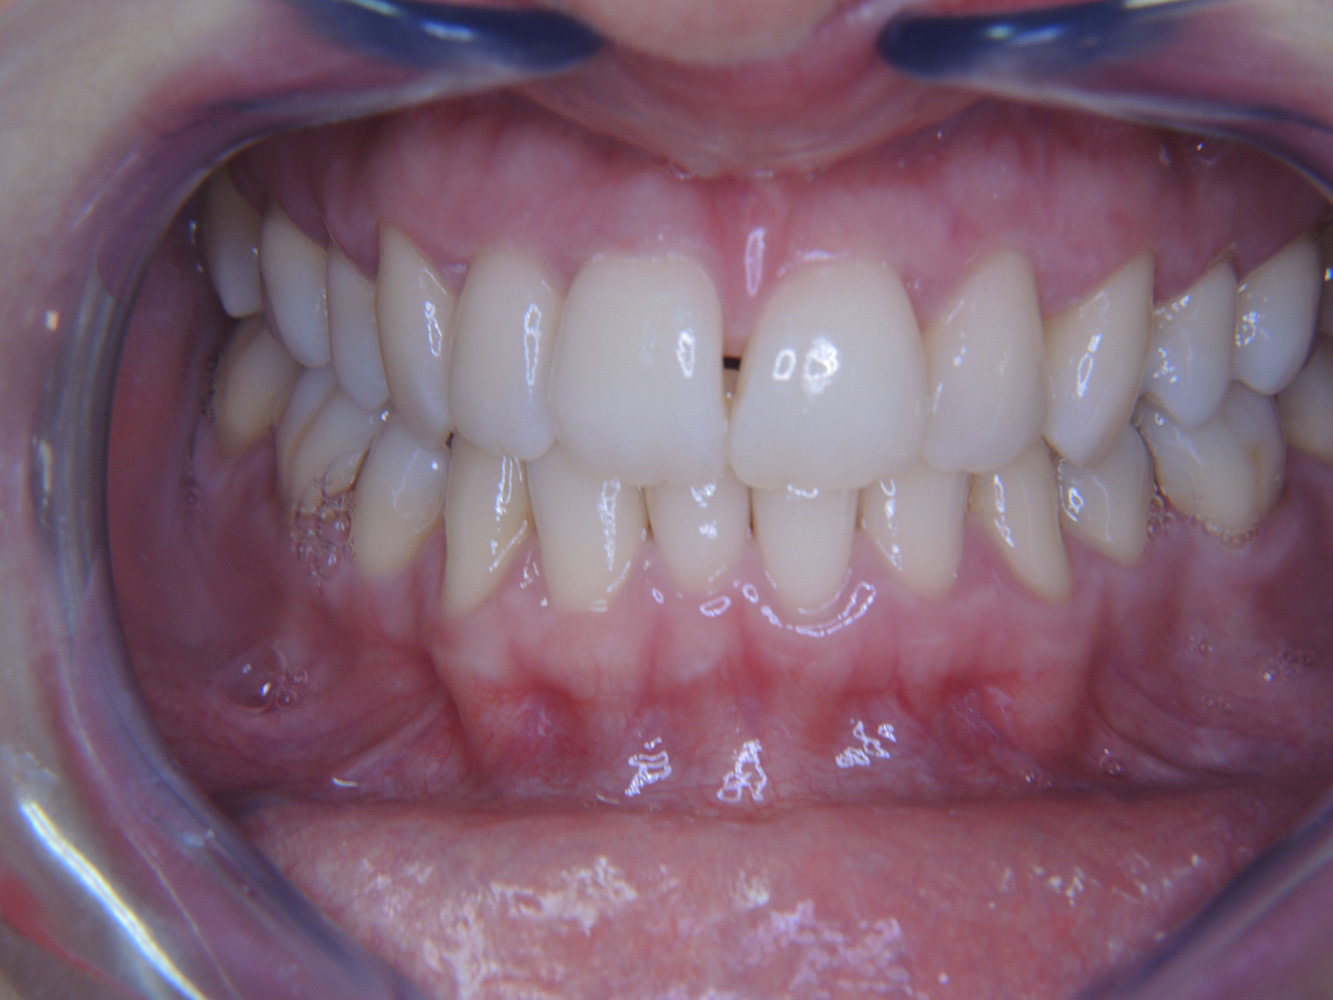

Der (mund)-gesunde Patient mit Implantaten

Der 55-jährige Patient gibt in der Anamnese an, keine Allgemeinerkrankungen zu haben und keine Medikamente einzunehmen. Die Lebensgewohnheiten des Patienten sind ebenfalls unauffällig. Der Patient hat einige zahnärztliche Restaurationen und zwei Implantate (2. und 4. Quadrant). Anhand der aktuellen Befunde lässt sich eine Gingivitis bei stabilem parodontalen Zustand am reduzierten Parodont (Stadium III, Grad A) feststellen. mehr Infos